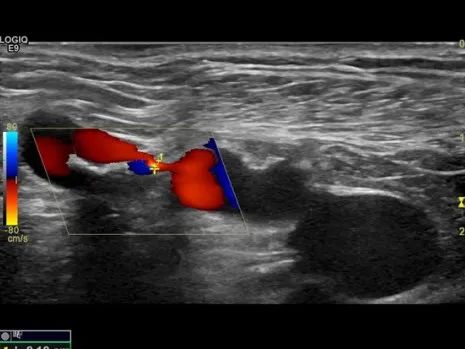

超声:右股动脉血流量499ml/min,右头静脉弓重度狭窄,最窄处病变直径约1mm

1/ 超声引导下顺行穿刺右上臂头静脉,置入8F血管鞘,建立入路;